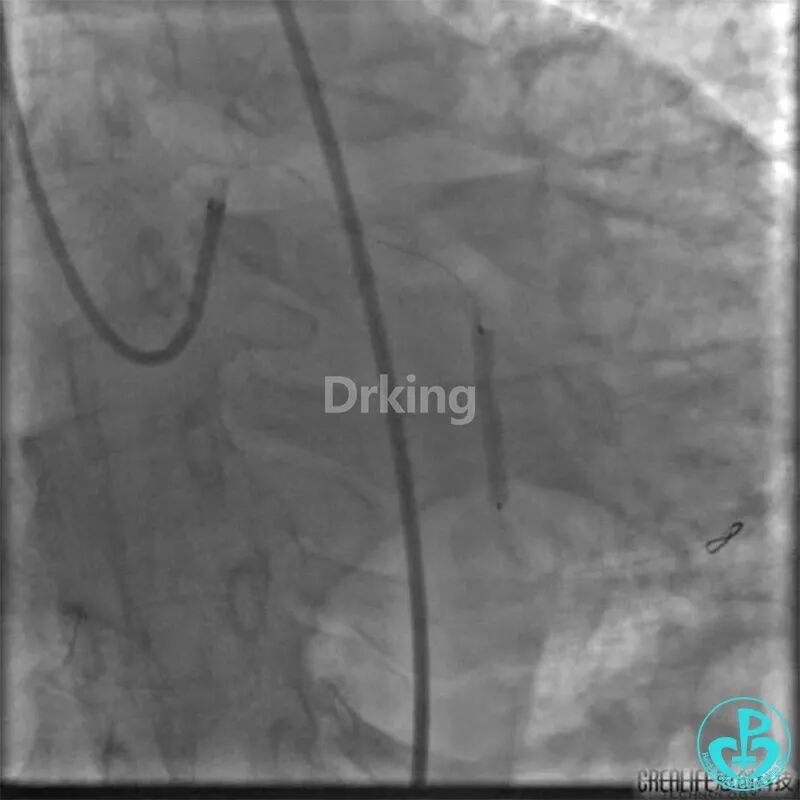

把Sion导丝送至高位OM的远段,在双腔微导管的辅助支撑下,把BMW导丝通过LCX扭曲及病变处顺利送至远段,撤出双腔微导管,2.0×20mm球囊对病变处PTCA后狭窄减轻,于病变处植入2.75×23mm支架一枚,后分别用2.75×12mm、3.0×12mm球囊对支架内后扩,复查造影原病变处狭窄消失,TIMI血流三级。

冠脉严重扭曲病变导丝通过困难时,策略技巧如下:

1. 强有力的大腔支撑;

2. 导丝反复塑形,如该病例中导丝塑成天鹅颈形状;

3. 球囊封堵分支开口;

4. 微导管、抽吸导管、双腔微导管等辅助支撑与引导,尤其巧用分支血管利用双腔微导管也是一高招。